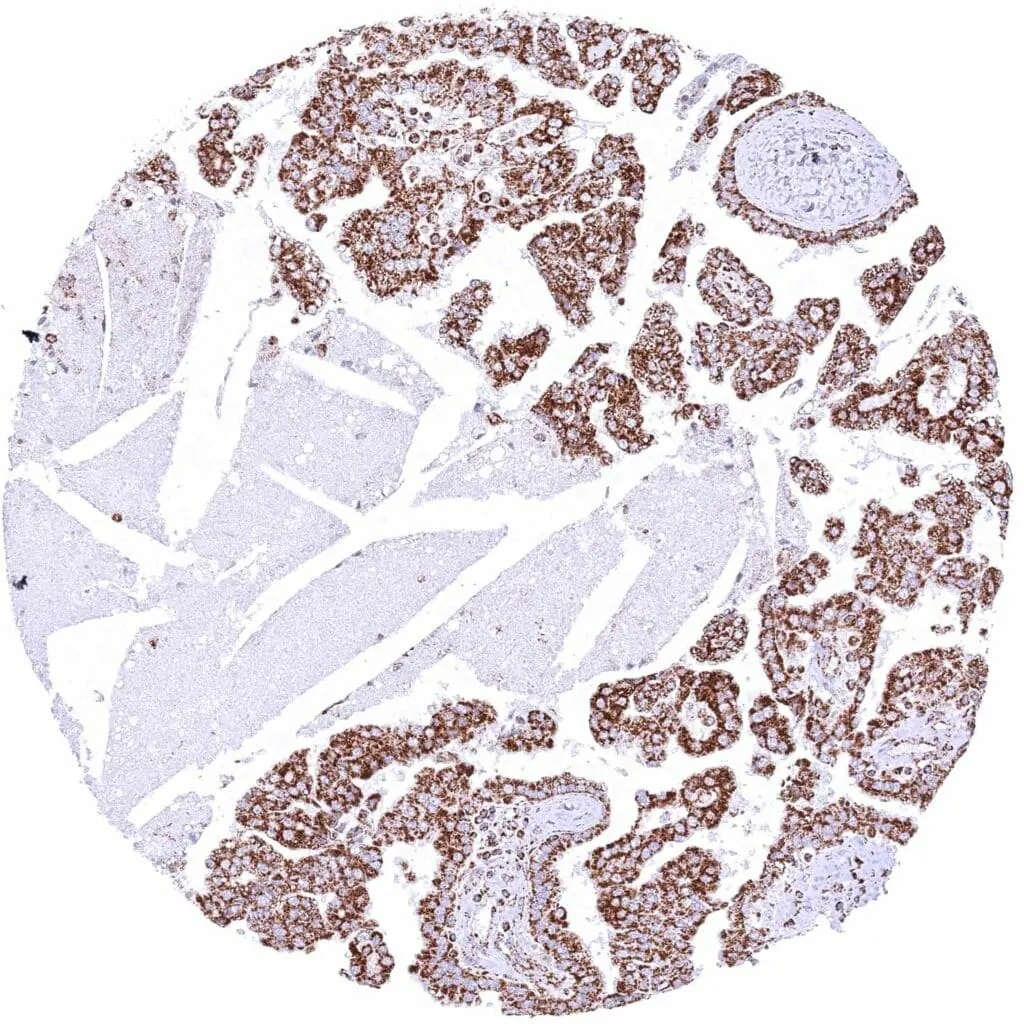

Kidney – Clear cell renal cell carcinoma with weak to moderate cytoplasmic ATP5J immunostaining of tumor cells.